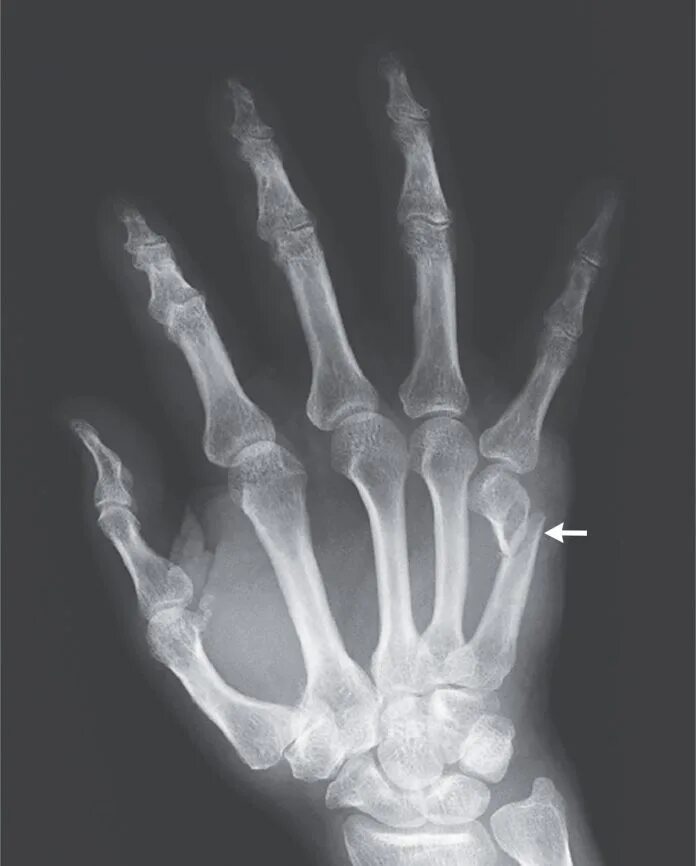

Перелом пятой пястной кости